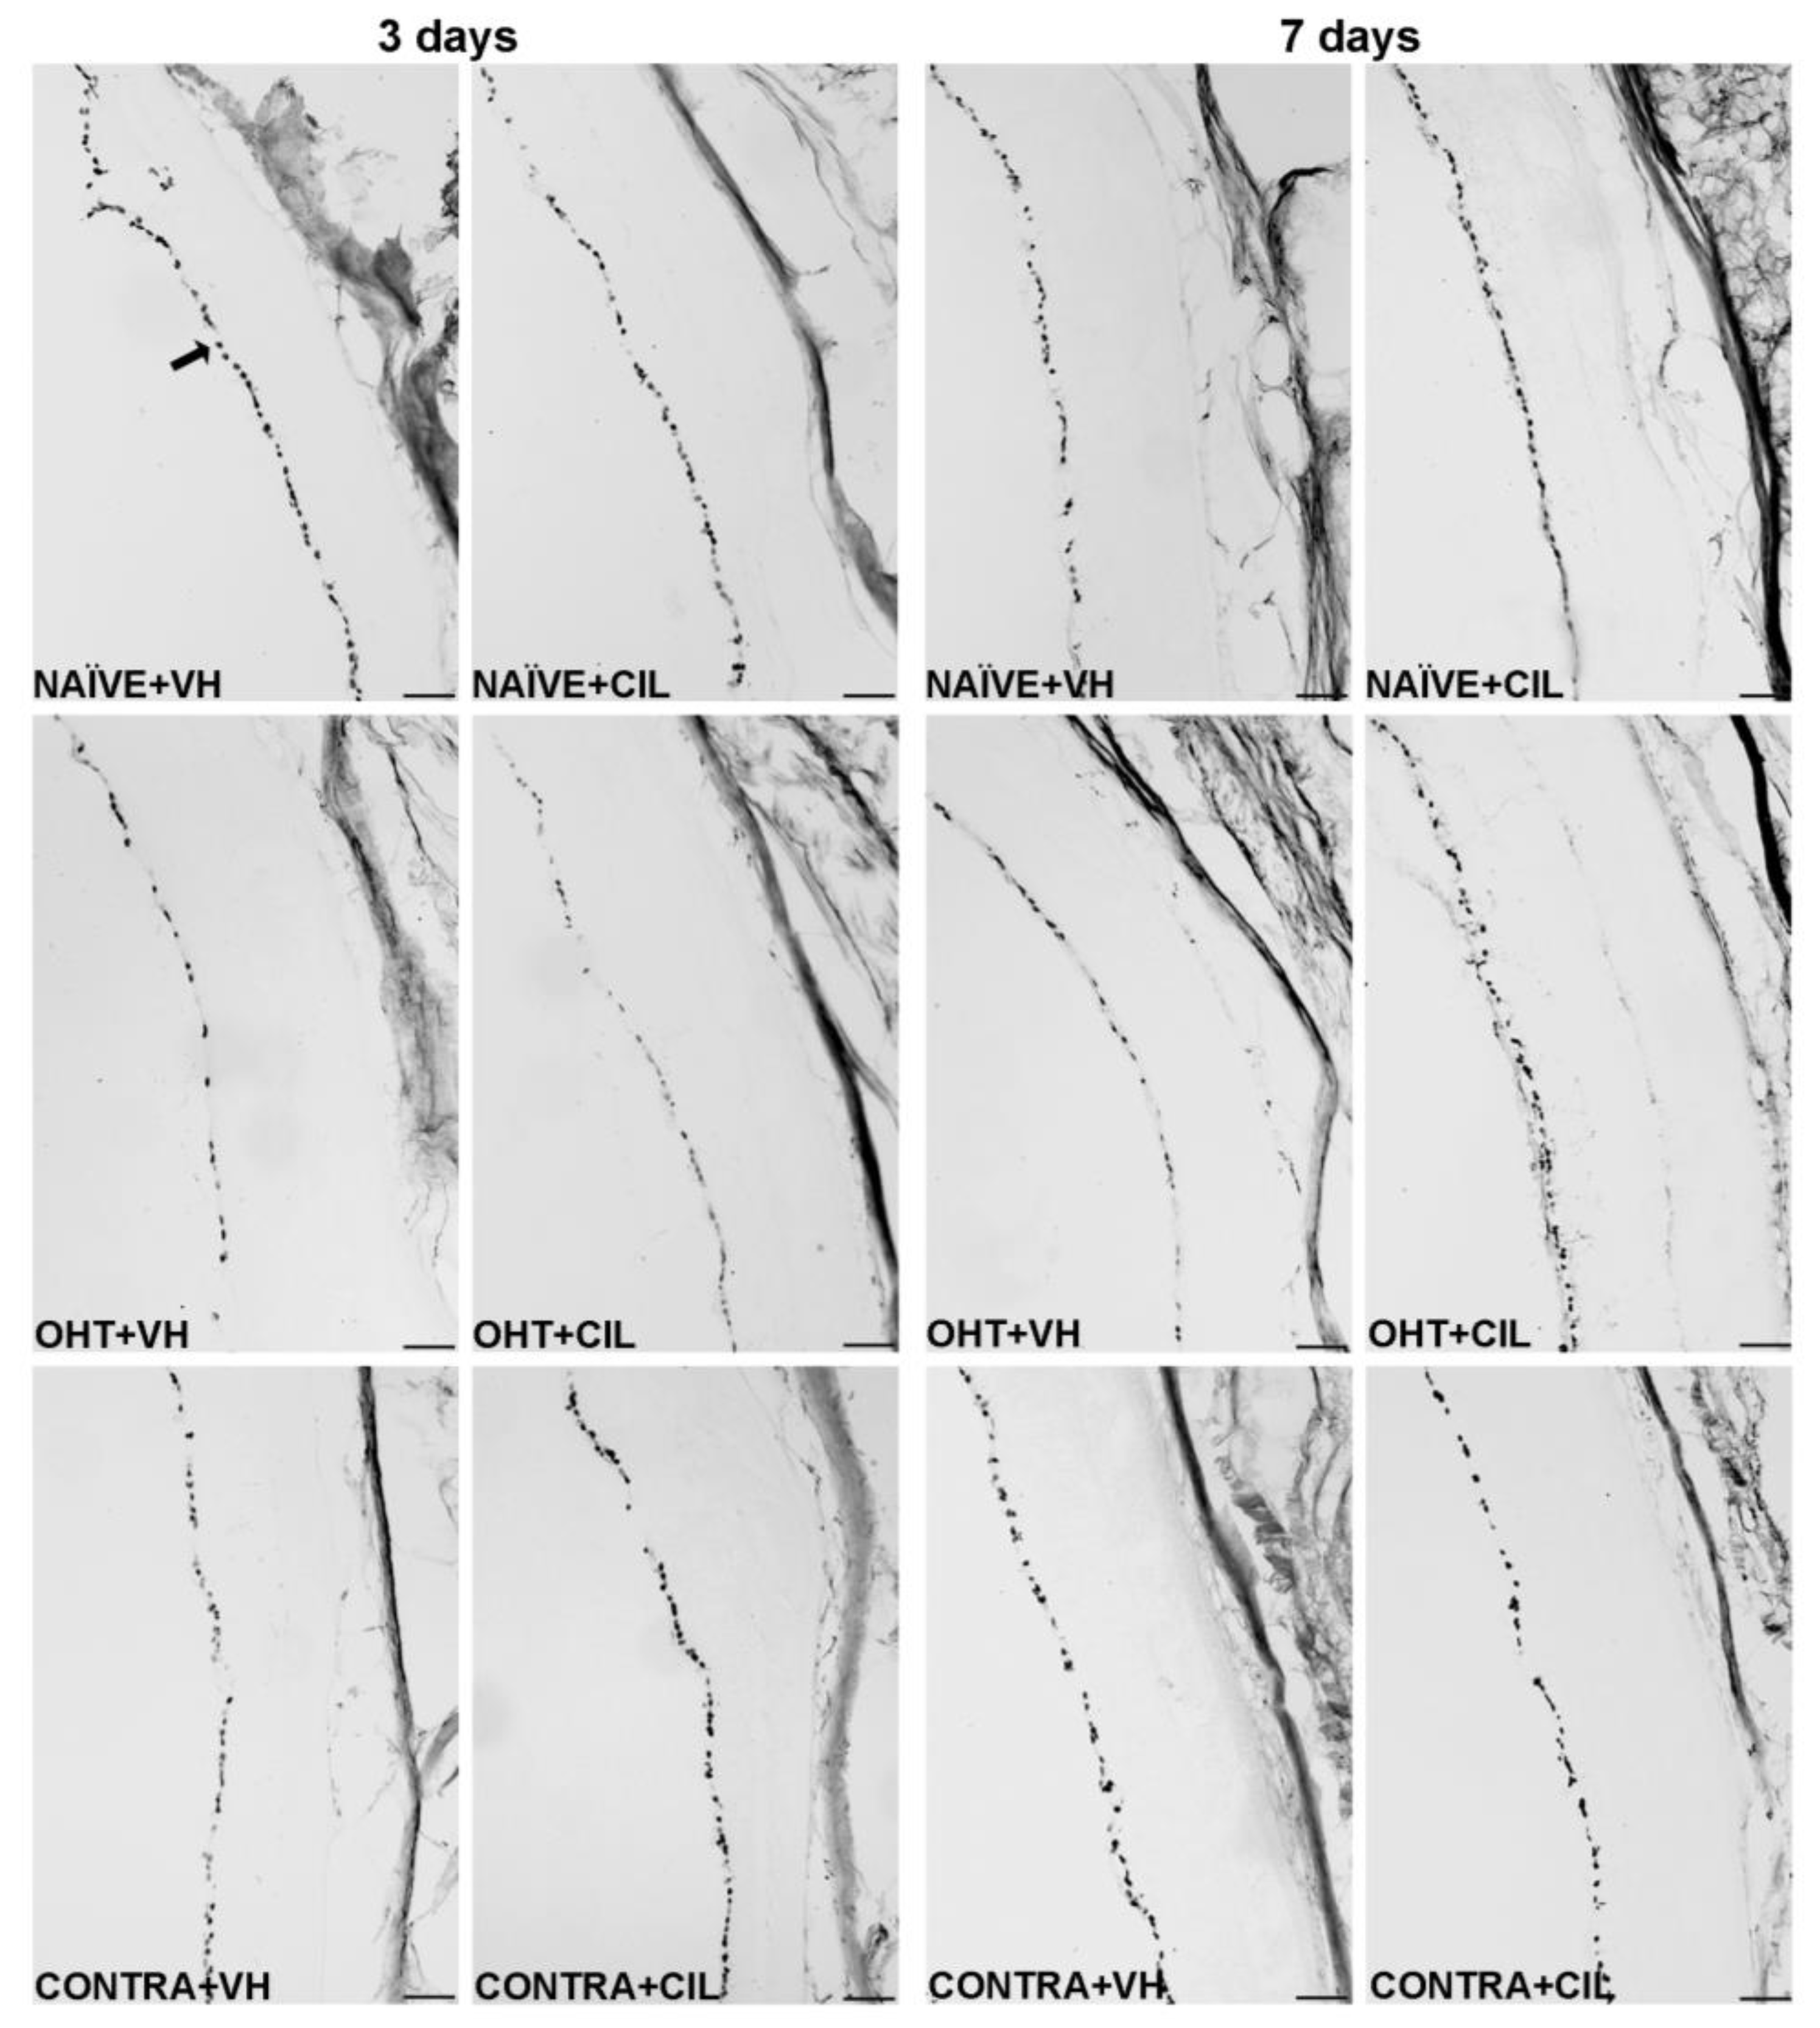

Figure 8. Iba-1+ cells in the total retina. Iba-1+ cells were measured in the left photocoagulated eye (laser-induced ocular hypertension, OHT), and its contralateral (CONTRA). Data also include a group of non-manipulated (NAÏVE) mice. Animals were administered cilastatin (CIL, 300 mg/kg, i.p.) or vehicle (VH, saline) daily two days before the surgery until sacrifice 3 or 7 days after OHT induction; i.e., animals received 6 or 10 injections, respectively. Microphotographs taken at 20× magnification show the main general results of the Iba-1 (ionized calcium-binding adapter molecule 1) immunohistochemical assay of the different experimental groups 3 and 7 days after OHT induction, where the main effects can be appreciated in the graph. In the 3 days NAÏVE + VH microphotograph, the arrowhead points to the optic nerve fiber layer–retinal ganglion cell layer. In the 3 days OHT + VH image, the arrow points to an example of a microglial cell. Scale bar: 50 μm.

2.4. Analysis of Microglial Cells: Iba-1+ Expression

Results of Iba1+ expression are shown in Figure 7 and Figure 8 and Table S4. Three days after the surgery, we found that OHT + VH retinas expressed a significantly higher number of Iba-1+ cells compared to NAÏVE + VH eyes (p < 0.001), and CONTRA + VH eyes also exhibited an increased number of Iba-1+ cells than NAÏVE + VH eyes (p < 0.001). CIL administration was able to prevent and/or revert such an increase (OHT + CIL vs. OHT + VH eyes, p < 0.001; CONTRA + CIL vs. CONTRA + VH eyes, p < 0.001). Similar results were found seven days after OHT induction: OHT + VH eyes exhibited a significantly higher number of Iba-1+ cells than NAÏVE + VH eyes (p < 0.001), CONTRA + VH eyes also showed a significant increase, although milder, in the number of Iba-1+ cells compared to NAÏVE + VH eyes (p < 0.001) and, in both cases, CIL was able to prevent and/or revert such effects (OHT + CIL vs. OHT + VH, p < 0.001; CONTRA + CIL vs. CONTRA + VH, p < 0.001).

In the further regional analysis, three days after OHT induction, we observed that the number of Iba-1+ cells was significantly and remarkably increased in all retinal regions when compared to NAÏVE + VH eyes. CONTRA + VH eyes also showed a significant although milder effect on the number of Iba-1+ cells; i.e., there was an increase in some nasal and central regions of the retina, but not in temporal regions. Samples receiving CIL did not exhibit a surgery-induced increase in Iba-1+ cells, as was the case for OHT eyes and CONTRA eyes (see Figure 7 and Table S4 for statistical details). Seven days after OHT induction, the increase in the amount of Iba-1+ cells was still present in OHT + VH eyes in all retinal regions, and the increase in the number of Iba-1+ cells in CONTRA + VH eyes was restricted to the C-C and T-S regions; in all cases, such an increase in the number of Iba-1+ cells was blocked and/or attenuated by the pharmacological treatment with CIL (see Figure 7 and Table S4 for statistical details). Results with non-relevant biological information are not shown.

The distribution of Iba-1+ cells within specific retinal layers was also investigated, and these microglial cells in OHT eyes appeared to be mainly detected within the ONFL-GCL, IPL, OPL and ONL-PL groups, both at three and seven days after the surgery. In CONTRA + VH eyes, the increase in Iba-1+ cells was only detected in IPL and OPL layers at three days after the surgery and exclusively in the IPL at seven days after the surgery. CIL administration avoided this surgery-induced increment in Iba-1+ cells in all these retinal layers, both in OHT and CONTRA eyes (Figure 9, consult Table S5 for statistical details). Results with non-relevant biological information are not shown. Microglial morphotypes were also investigated, and RD microglial cells were detected as the majority, followed by HZ microglial cells, with a low percentage of VT cells. No differences in this pattern of microglial morphotypes were observed due to the surgical intervention or due to CIL treatment at any time point.

3.5. Cilastatin

CIL seemed to attenuate the effects of OHT induction on microglial cells in both OHT and CONTRA eyes at both time points. In further regional and layer analyses, CIL seemed to revert most of these changes, suggesting anti-inflammatory effects, diminishing the microglial response in the retina. Even though it had a generalized response over all the retina, the effects appear to be more remarkable in areas closer to the optic disc, returning the microglial activation to values near to those observed in NAÏVE animals in both eyes.